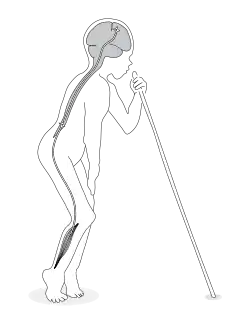

La aparición de parálisis (paraparesia espástica) es súbita y simétrica y afecta las piernas más que los brazos. Esto da como resultado inestabilidad la cual es permanente pero no progresa. Típicamente, el paciente esta quieto y estando caminando tiene la sensación de bolas en los pies con rigidez de las piernas y frecuentemente con clonus en las rodillas.

Inicialmente, muchos pacientes experimentan debilidad generalizada durante los primeros días y están postrados en cama por algunos días o semanas antes de tratar de caminar. Ocasionalmente presentan visión borrosa y dificultades en la emisión del lenguaje durante el primer mes, excepto en pacientes enfermos severamente. La espasticidad está presente desde el primer día, sin una fase inicial de flacidez. Después de las semanas iniciales hay mejoría de los síntomas, pero la paraparesia espástica permanece estable por el resto de la vida. Algunos pacientes pueden presentar abruptos episodios de agravamiento, por ejemplo un súbito y permanente empeoramiento de la paraparesia espástica. Cada episodio es idéntico a la presentación inicial y puede por lo tanto interpretarse como una segunda presentación.

- Leve: Cuando el individuo puede caminar sin apoyo.

- Moderado: Cuando el individuo necesita uno o dos bastones de apoyo para poder caminar.

- Severo: Cuando el individuo afectado es incapaz de poder caminar sin apoyo.